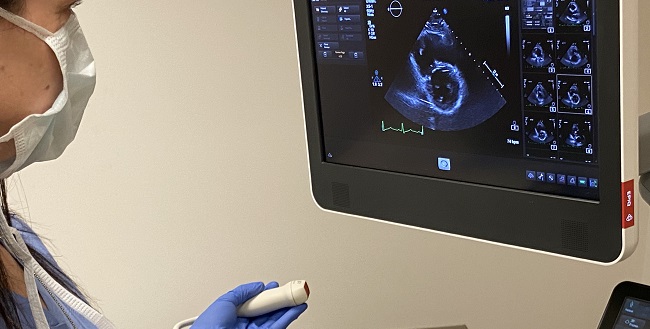

Top Stories in Cardiology: June 2020This month, Julia Grapsa and Mary Norine Walsh describe the many ways COVID-19 affects the heart. |